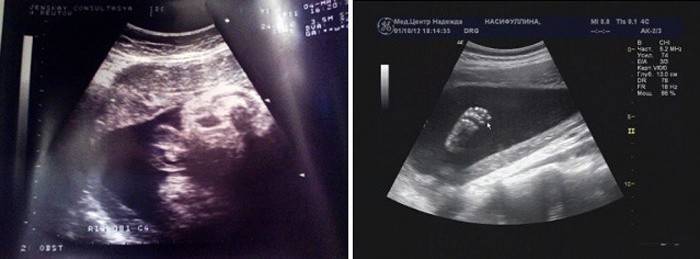

Ultrazvukové vyšetrenie (Uzi)

Zvyčajne je ultrazvuk v tomto období predpísaný na účely ďalšieho výskumu v prípade podozrenia na akékoľvek abnormality vo vývoji tehotenstva. Rozhodovanie o type dodávky alebo o akýchkoľvek ďalších cieľoch. Počas štúdie sa určujú ultrazvukové parametre - odhadovaná hmotnosť a výška plodu, norma frekvencie kontrakcií, stav placenty a pupočníka, množstvo plodovej vody, atď.

Obzvlášť dôležité je vyhodnotiť prácu placenty a jej stupeň zrelosti, preskúmať krčka maternice a stupeň zrelosti. Dešifrovanie ultrazvukových údajov vykonáva lekár, 3D ultrazvuk možno vykonať aj v tomto období, ale nie je možné vidieť celé dieťa, je príliš veľký.